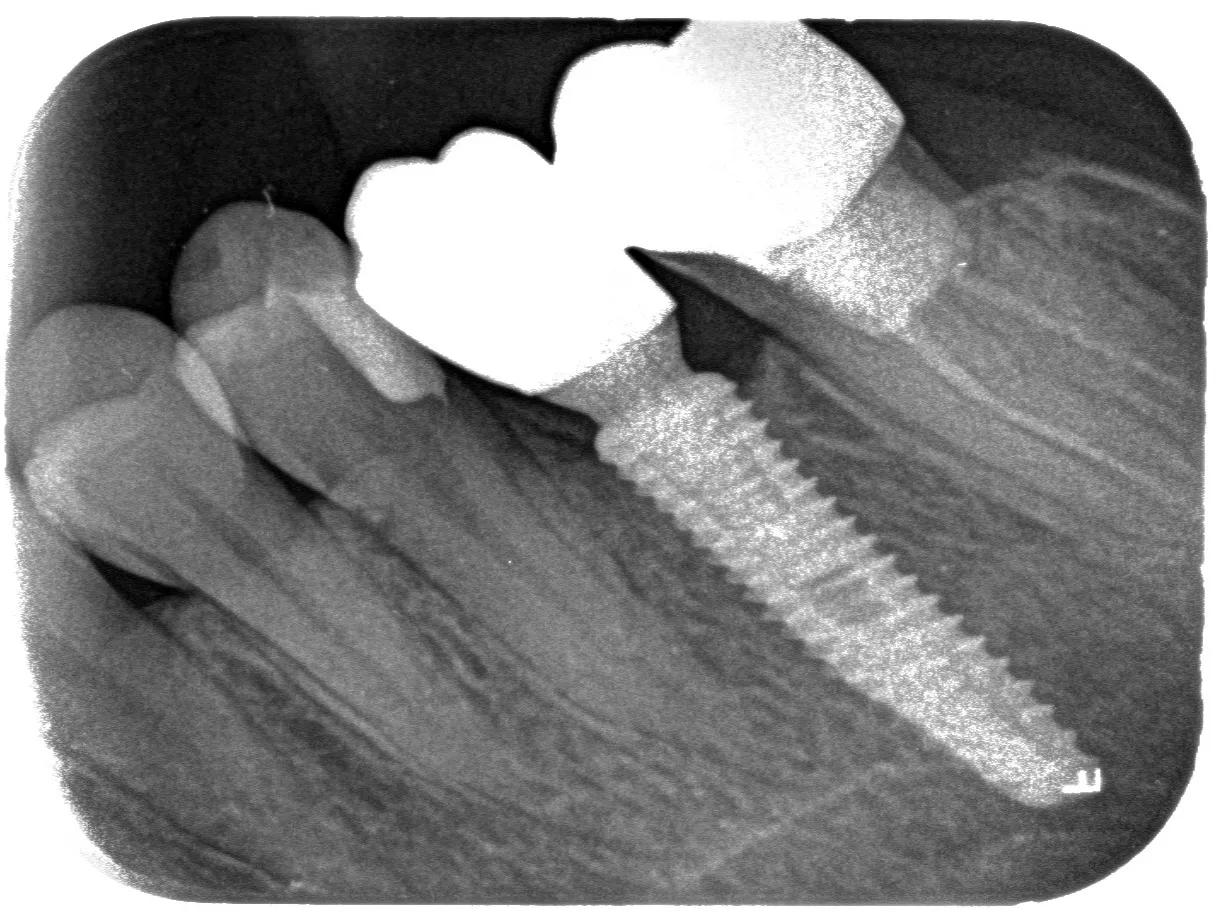

正式开始种植牙手术。在牙槽骨上制备一个孔,植入人工种植体。将牙骨床内严密缝合,大约一个星期后可以拆线。这次大概2个半月--3个月)

等待骨结合期。(这个时间的长短因人、因种植系统而异。有的人、有的种植牙系统系统要2--3个月;有的需要超过半年时间)